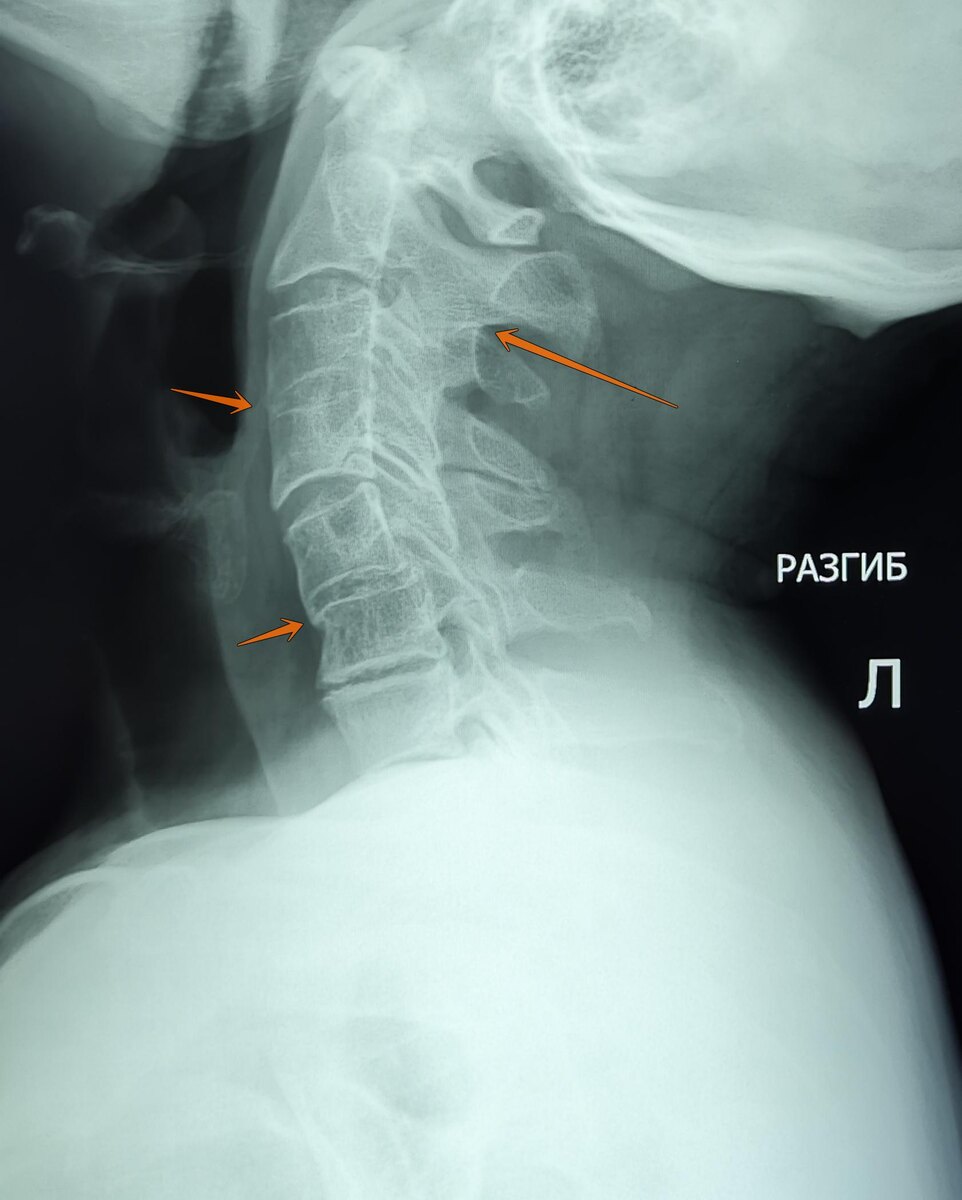

Пациент 65 лет, жалобы на боли, ограничение подвижности в ШОП.

На Р-граммах ШОП с функциональными пробами: лордоз нарушен в нижнем шейном отделе по типу кифоза. Структура тел сохранена, контуры позвонков ровные, четкие. Замыкательные пластинки склерозированы. Неравномерное умеренно снижена высота м/п пространств. Сращение остистых отростков С2-С3.Частичное сращение тел С3-С4 позвонков в переднем и заднем краях тел позвонков, за счет спондилеза. Частичное сращение передних краев тел С5-С6 позвонков за счет спондилеза. На функц.спондилограммах: отмечается умеренное ограничение подвижности в сегментах С2-С3,С3-С4,С5-С6 за счет синостоза. Заключение: Остеохондроз ШОП 2-3ст. ст. Спондилез. Спондилоартроз. Синостоз остистых отростков С2-С3.Частичный синостоз С3-С4,С5-С6.Умеренное ограничение подвижности в ШОП за счет синостоза.